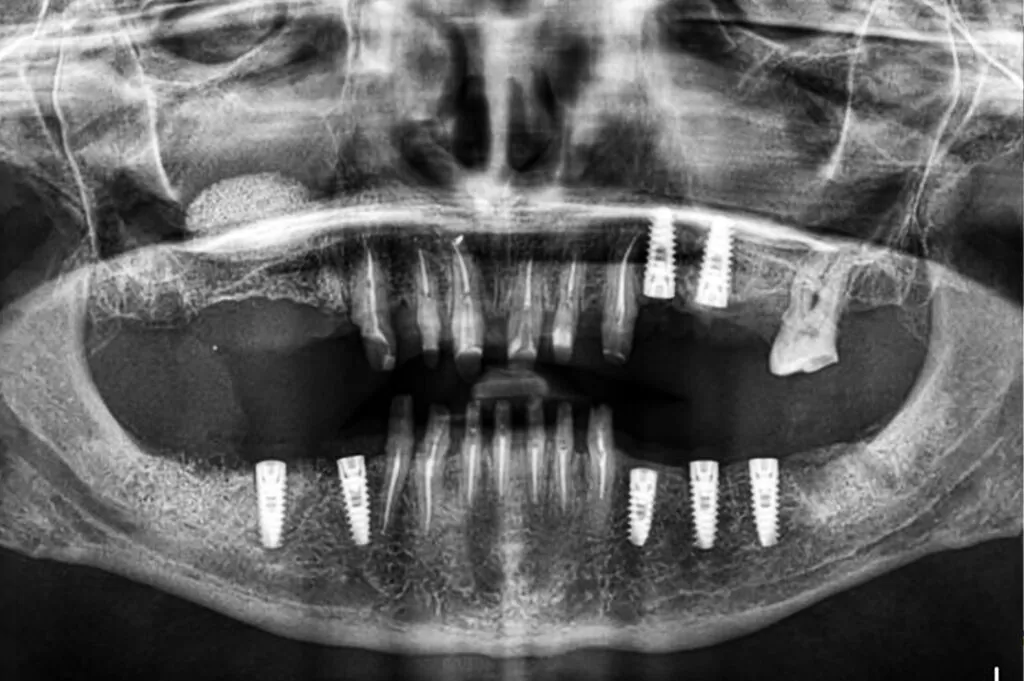

Implantul dentar reprezintă înlocuirea unuia sau a mai multor dinți pierduți din diferite cauze. Este un tratament pe care pacienții îl preferă datorită faptului că permite ca dinții sănătoși ce se află în vecinătatea celor implantați să nu aibă de suferit. Deși are o rată mare de succes, implantul dentar poate prezenta complicații.

Cele mai întâlnite complicații sunt cele de natură biologică.Aceste complicații se pot manifesta fie în perioada timpurie de după realizarea implantului, fie după mai mult timp. În această categorie pute regăsi:

• Periimplantita;

• Hemoragie;

• Afectarea nervilor (poate cauza durere, amorțeală și parestezie în țesuturi precum gingii, buze sau bărbie);

• Retracție gingivală;

• Lipsa oseointegrării (integrarea osoasă a implantului).